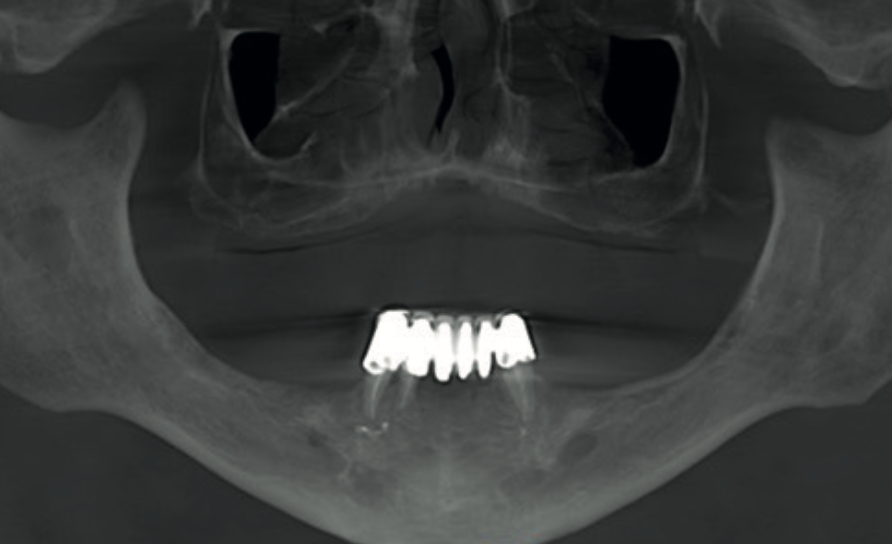

Thin-slice panoramic view showing bone assessment for implant planning Cross-sectional views confirming minimal residual alveolar ridge height in the maxilla

Fig. 2 & 3 Left: thin-slice panoramic view for implant bone assessment. Right: cross-sectional images of the upper incisor region confirm severely reduced alveolar ridge height — insufficient for implant anchorage.

Reformatted panoramic CBCT view showing edentulous maxilla and three remaining mandibular teeth

Fig. 1 Reformatted panoramic view from the CS 9600 showing the edentulous maxilla and three remaining mandibular teeth supporting a fixed prosthesis.